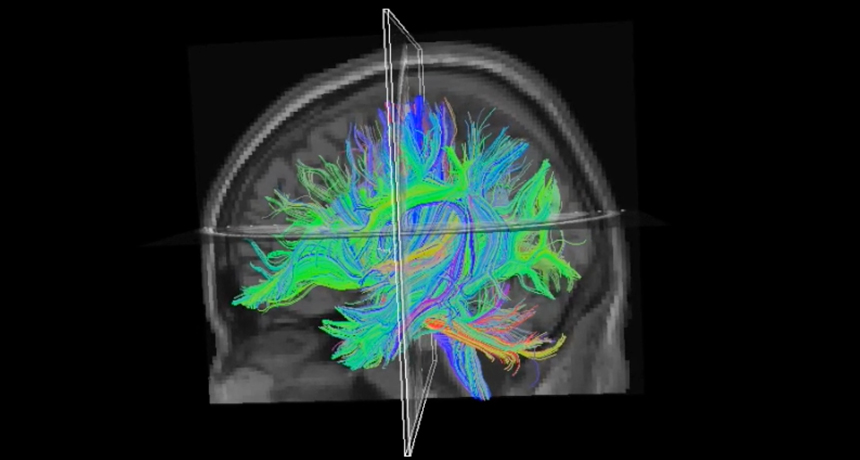

MISSING LINKS  Connections between language-processing regions of the brain (shown here as colored links in a diffusion tensor image) may be broken in people with dyslexia, new research finds.

Courtesy of KU Leuven